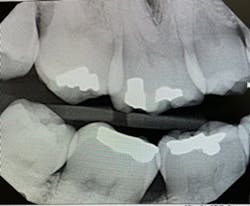

Literature suggests using the “open-door method” when contacts need to be clear and diagnostic.5 This method is achieved by moving the sensor distomesially by 15 degrees to ensure the canine is visible. This will keep the interproximal spaces open in the premolar bitewing. To avoid horizontal overlap, the central ray should be perpendicular to the arch of the teeth and directly through the interproximal spaces. With proper training and education on the concepts to mitigate overlapping, we can avoid exposing our patients to unnecessary radiation. Unfortunately, because the angle of the PID is off in Figure 1, the patient will need to be exposed to another radiograph. Proper angulation is shown in Figure 2, and proper positioning of the open-door method is shown in Figure 3.

“Horizontal angulation refers to the positioning of the PID and the direction of the central ray in a horizontal, or side to side, plane.”6 Paralleling, bisecting, and bitewings all use similar principles of horizontal angulation and will not change according to technique. The PID needs be directed toward the center of the ring using a horizontal/parallel technique. With this correct angulation, proximal spaces will be cleared, and the radiopaque enamel with either be just touching or have a distant radiolucent line of separation. This will produce a diagnostic image (figure 4) where calculus or caries lesions will not go undetected.